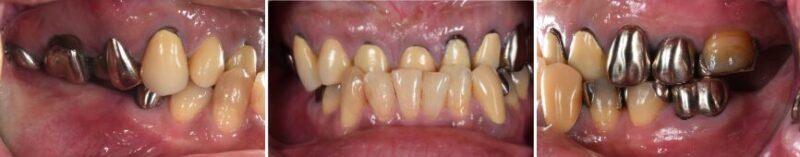

今回ご紹介する患者さんは40代の男性で、奥歯の欠損と歯並びの乱れによってかみ合わせが不安定な状態でした。奥歯がないことで、しっかり噛むことが難しく、全体のバランスも崩れていました。

※初診時の口腔内とレントゲンの写真